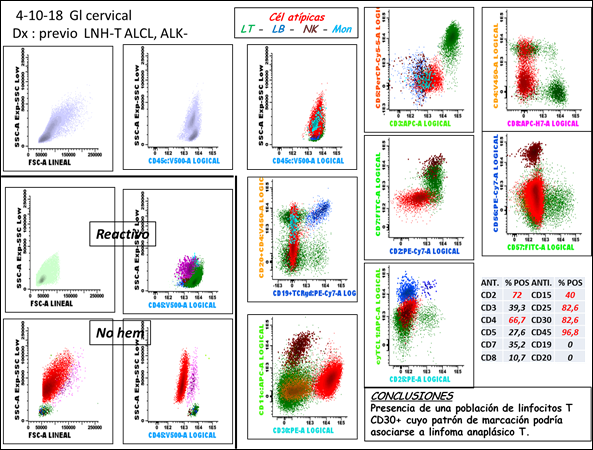

Hallazgos de citometría de flujo (CMF):

En octubre de 2018 recibimos una biopsia de ganglio cervical del paciente que tenía diagnosticado un LNH-T anáplasico ALK-.

Lo primeros que hicimos por CMF fue mirar los parámetros de dispersión de luz FSC/SSC y la expresión de CD45 el antígeno pan leucocitario en analogía con lo que se hace por morfología y remedando una hematoxilina/eosina. Nos encontramos con células de gran tamaño (comparándolo con ganglios reactivos) y que expresaban intensamente CD45 en comparación con una infiltración por células de estirpe no hematológicas.

Ensayando los marcadores de estirpe linfoide, siguiendo un código de colores en los gráficos puntos azules para marcadores de células B: CD19 y CD20, puntos marrones para marcadores de célula NK relacionados con citotoxicidad: CD56, CD57 y CD11c (CD94 granzima y perforina) en ambas poblaciones fueron negativos. Pero también los marcadores para células T (en puntos verdes) CD7 CD2 CD3 CD5 CD8 todos ellos fueron negativos. Sólo expresaban CD4 de manera parcial y por lo tanto y como están descriptos en la literatura este fenotipo correspondería a células nulas. Sin embargo, la expresión de CD30 fue contundente para confirmar la infiltración de acuerdo con el antecedente y presunción diagnóstica.

Cabe destacar que la expresión de CD30 no es exclusiva de los ALCL y que, a diferencia de las células de Reed-Stemberg, por ejemplo, éstas suelen ser CD45 negativas y expresar de manera intensa CD15.

A modo de referencia vemos en el cuadro de la derecha la frecuencia de expresión reportada en la literatura para una media de 50 casos.

Desde el punto de vista de la CMF, salvo por la expresión de CD45, CD30, CD25, CD2 y CD4 que superan el 50%, y que en nuestro caso NO expresaba CD2 NI CD25, no podríamos asegurar que la marcación correspondiera inexorablemente a un LNH-T anaplásico, aunque podría corresponder, la interpretación diagnóstica de estos hallazgos debe hacerse en el contexto clínico/morfológico (Figura 4).

Figura 4. Hallazgos de citometría de flujo